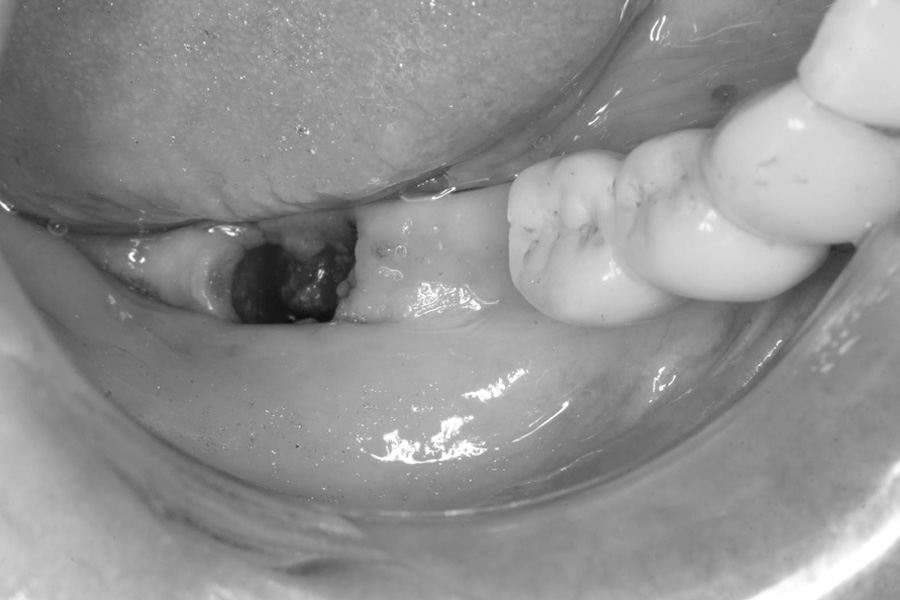

治療前

治療前症例写真

抜歯直後

抜歯直後症例写真

ブリッジの土台にしていた歯の保存ができなくなり、再治療を行いました。

右下3番、7番の抜歯後、右下3番、5番、6番相当部分にインプラントを3本埋入し、補綴を行いました。